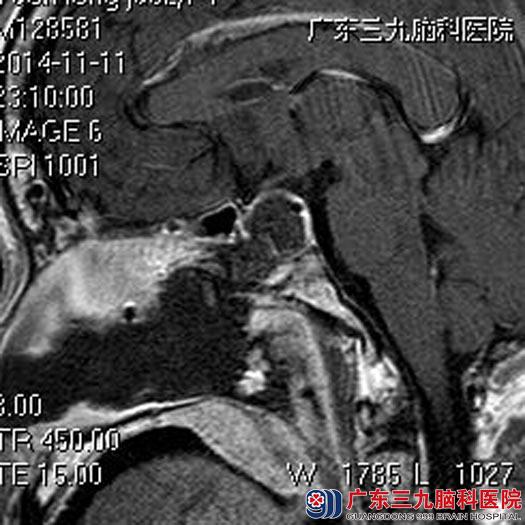

第二天,陈先生便带着母亲到当地医院,头颅CT检查提示鞍区占位,考虑垂体瘤可能性大。为进一步治疗,陈先生又带着母亲来到广东三九脑科医院垂体瘤诊疗中心。查体:脸面部颧骨增大、鼻梁增粗、四肢指端肥大,握拳不能,粗侧双眼视力0.8,视野基本正常。头颅MR检查提示:鞍区(鞍内为主)一结节状占位性病变,大小约1.8cm×2.4cm×2.4cm,右侧颈内动脉部分被包绕,行内分泌检查提示生长激素、泌乳素增高。